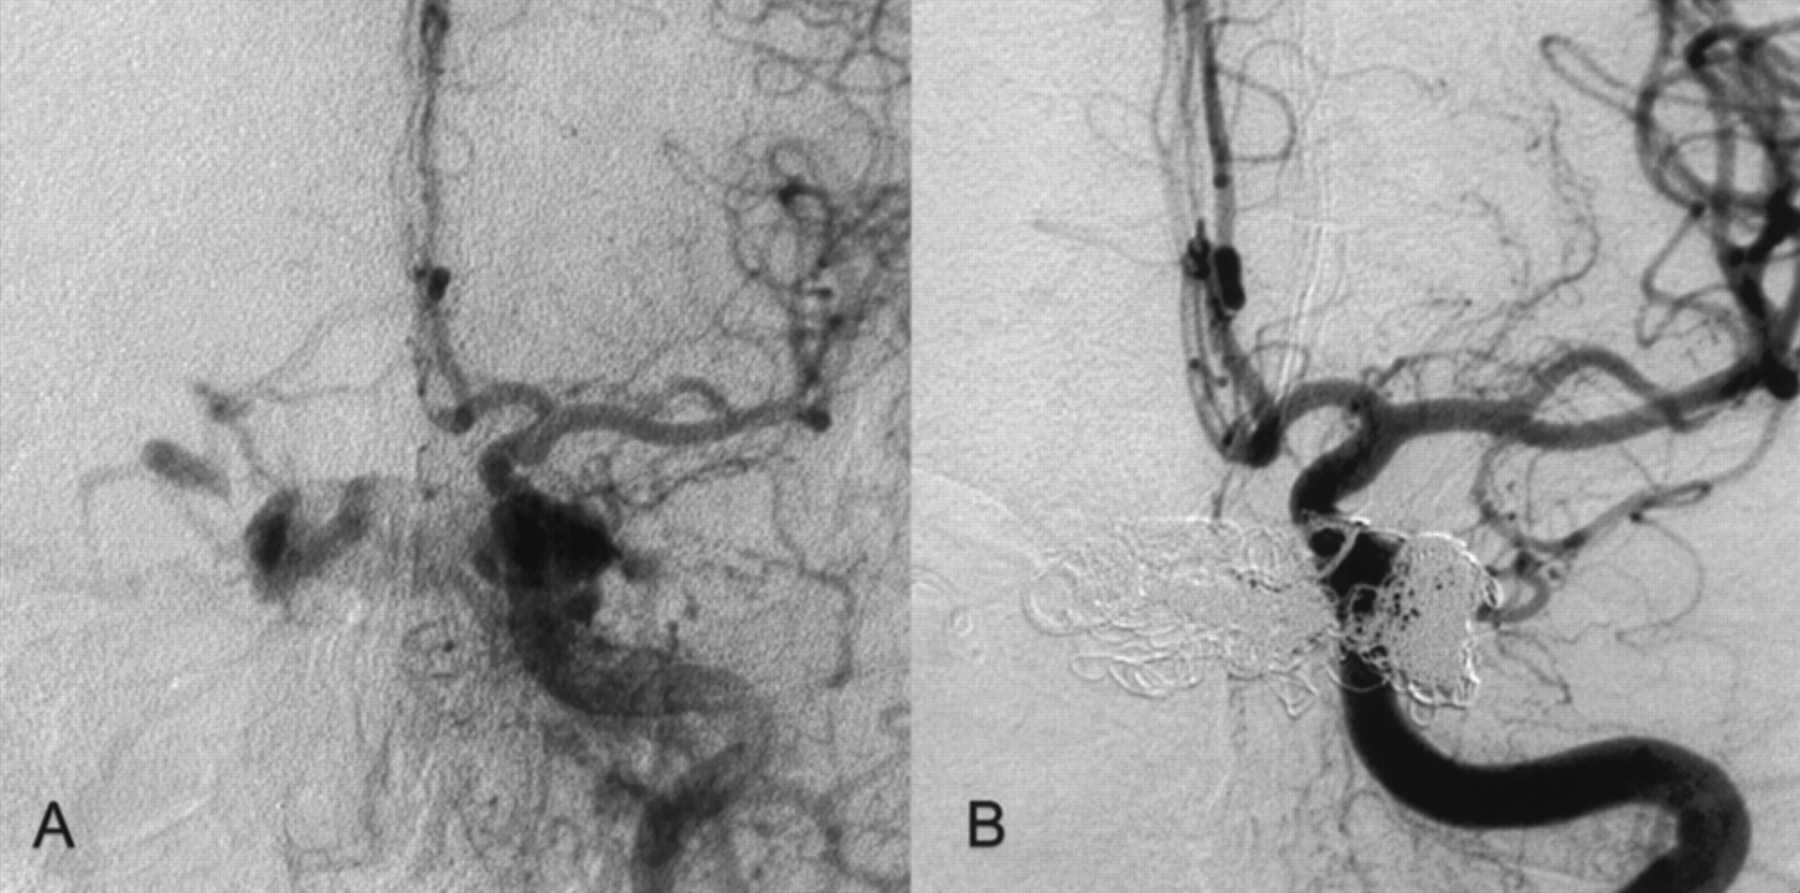

Two months before admission, a 74-year-old woman developed diplopia, exophthalmus on the left side, scotomas, left visual blur, and left conjunctival injection. MR imaging, MR angiography, CT, and duplex sonography revealed a CCF. At the time of admission, the patient had exophthalmus on the left, visual disturbance, diplopia, bilateral abducens nerve palsy, and left oculomotor nerve palsy. Angiography revealed a Barrow type D CCF with bilateral fistulae of the cavernous sinus fed by multiple meningeal branches of the external carotid artery on both sides, by the anterior meningeal branch of the left vertebral artery, and by the internal carotid artery on the left side (Figs 1 and 2). The CCF drained from the cavernous sinus into the right SOV, the left pterygoid venous plexus, the left inferior petrosal sinus, and via cortical veins into the straight sinus and the lateral sinuses on both sides. The right inferior petrosal sinus could not be detected. In contrast to the initial MR angiography performed 4 weeks earlier, the angiography showed the left SOV being thrombosed.

Right CCA.

A, Before treatment.

B, After successful CCF treatment.

However, the CCF could not be occluded despite the deployment of another nine GDCs. Therefore, a second microsurgical approach via the thrombosed left SOV was attempted. The surgical procedure was performed as on the contralateral side; however, the thrombosed SOV was not easy to detect and prepare. Intraoperative micro-Doppler imaging confirmed the thrombosis of the left SOV. The vein was punctured nevertheless, and under fluoroscopy, a microguidewire could be pushed forward through the soft thrombus. This allowed intracavernous placement of a two-tip Tracker 18, with successful endovascular occlusion of the CCF being achieved after an additional deployment of eight GDCs (Figs 1 and 2).

In total, the Barrow type D CCF was cured in three sessions with 35 GDCs (23 standard coils and 12 vortex coils; Boston Scientific, Fremont, CA) and with Ethibloc.